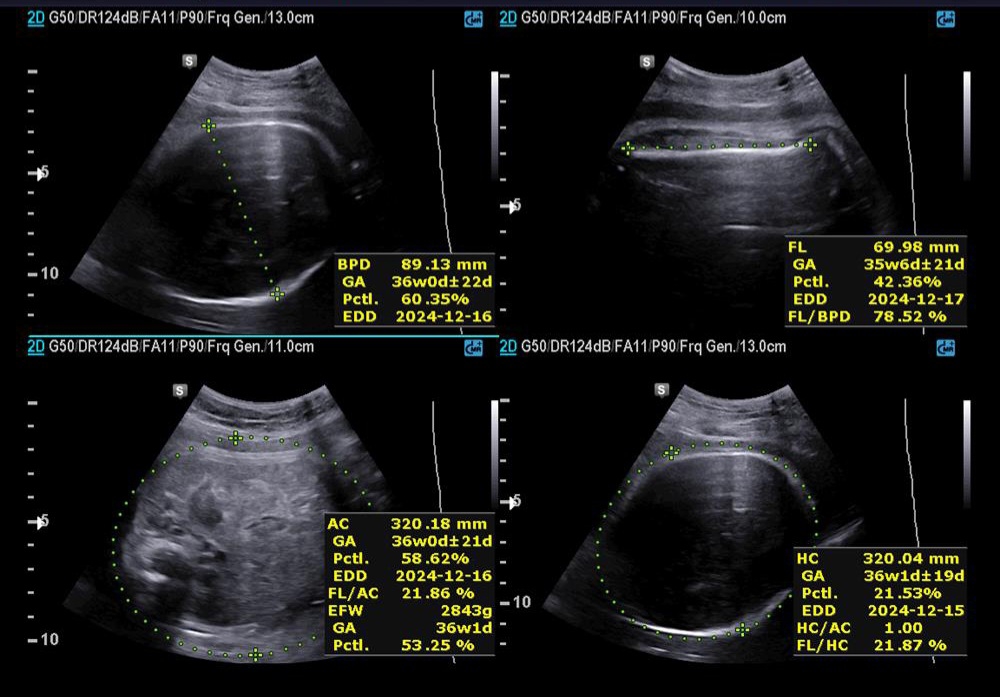

طبق lmp امروز ۳۶ هفته و ۳ روز بودم.

✅️✅️✅️تفسیر سونو داپلر۳۶ هفته🙏🏻

خداروشکر شواهد رشدی بهتر شده و در سونوگرافی شواهدی به نفع محدودیت رشد داخل رحمی و همچنین کمبود اکسیژن جنین وجود ندارد ولی مقداری مقاومت شریانی دارید به پزشکتان حتما مراجعه کنید تا درمورد زایمان و یا شروع انوکساپارین تصمیم گیری شود

جانم pi 2.4 ولی تحت نظر باشید مشکلی ندارد